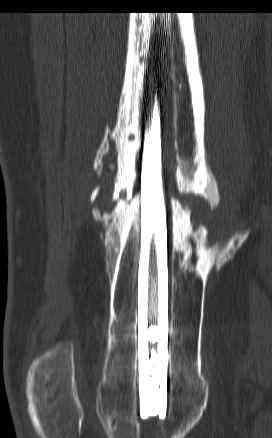

16 yr old boy, high energy motorcycle trauma trauma in July 2005 with:

- distal femoral fracture L

feb 07: retrograde nail + bone graft + BMP

nov 07: persistant non-union distal femur; other fractures healed uneventfully.

This is a true atrophic pseudoartrosis (without pain).

This fracture have a two factors failure combination.

The mechanical factor failure and the biological factor failure.

The solution need a combination of treatments which give solutions for each factor failure.